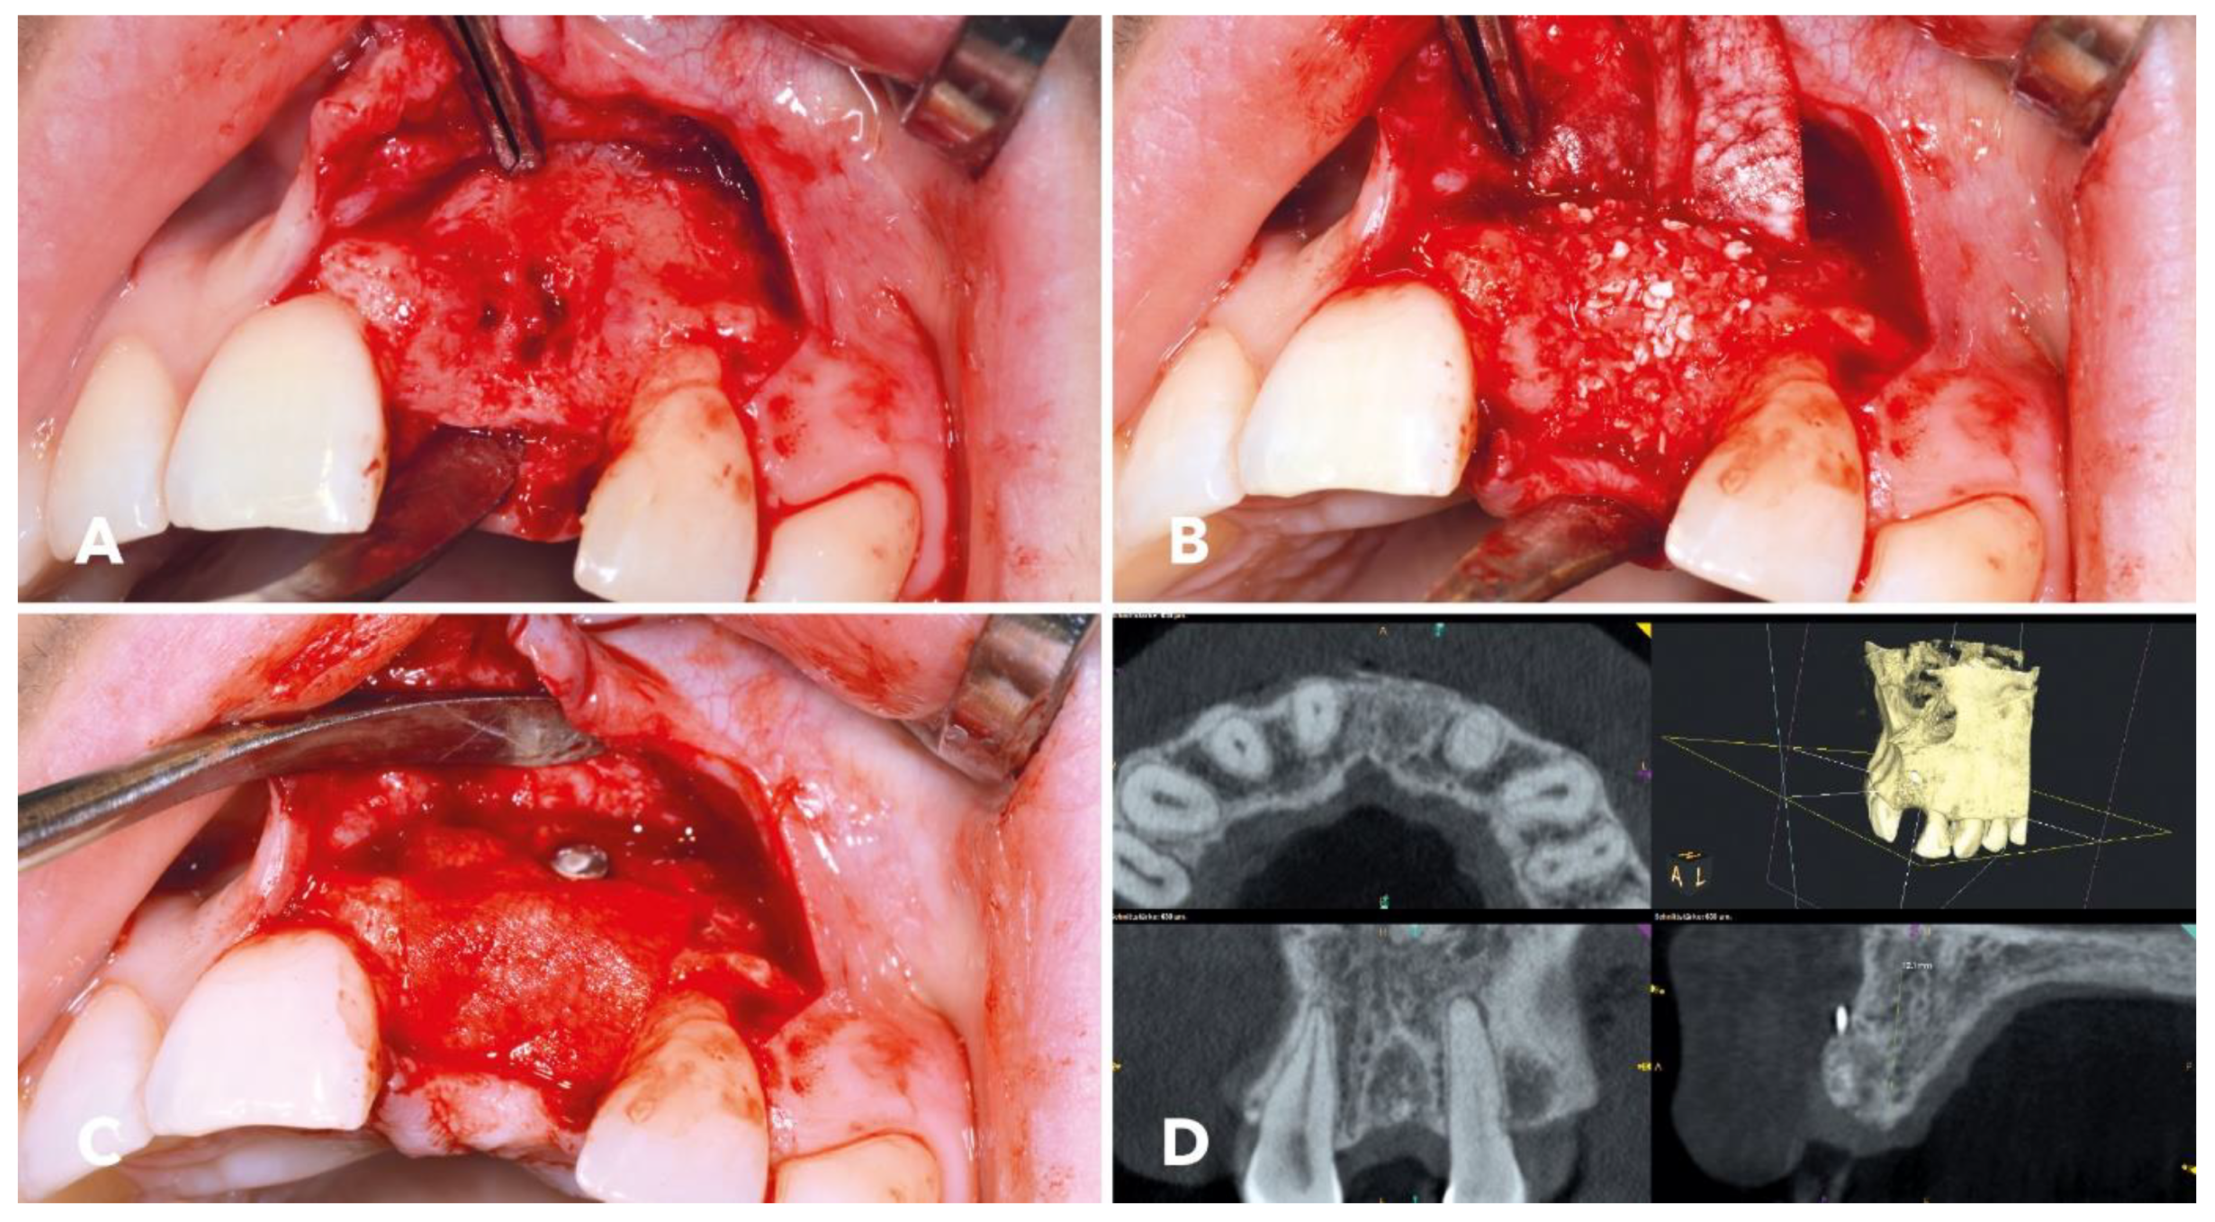

2.4. Surgical Procedure

2.5. Implantation